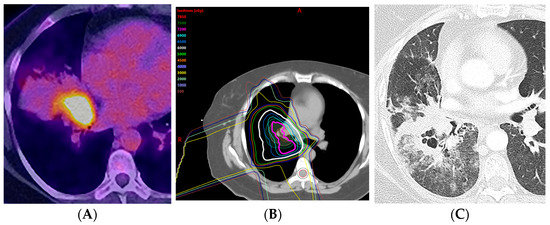

2.4. Stereotactic Body Radiotherapy

2.5. Four-Dimensional Conformal Radiotherapy

5.3. Positron Emission Tomography/Computed Tomography